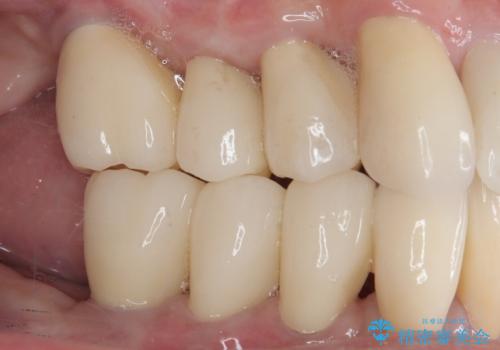

歯周病でグラグラの歯 矯正治療と歯周外科を併用した総合歯科治療

最終的には痛みや違和感のない状態にて治療を終えることができました。